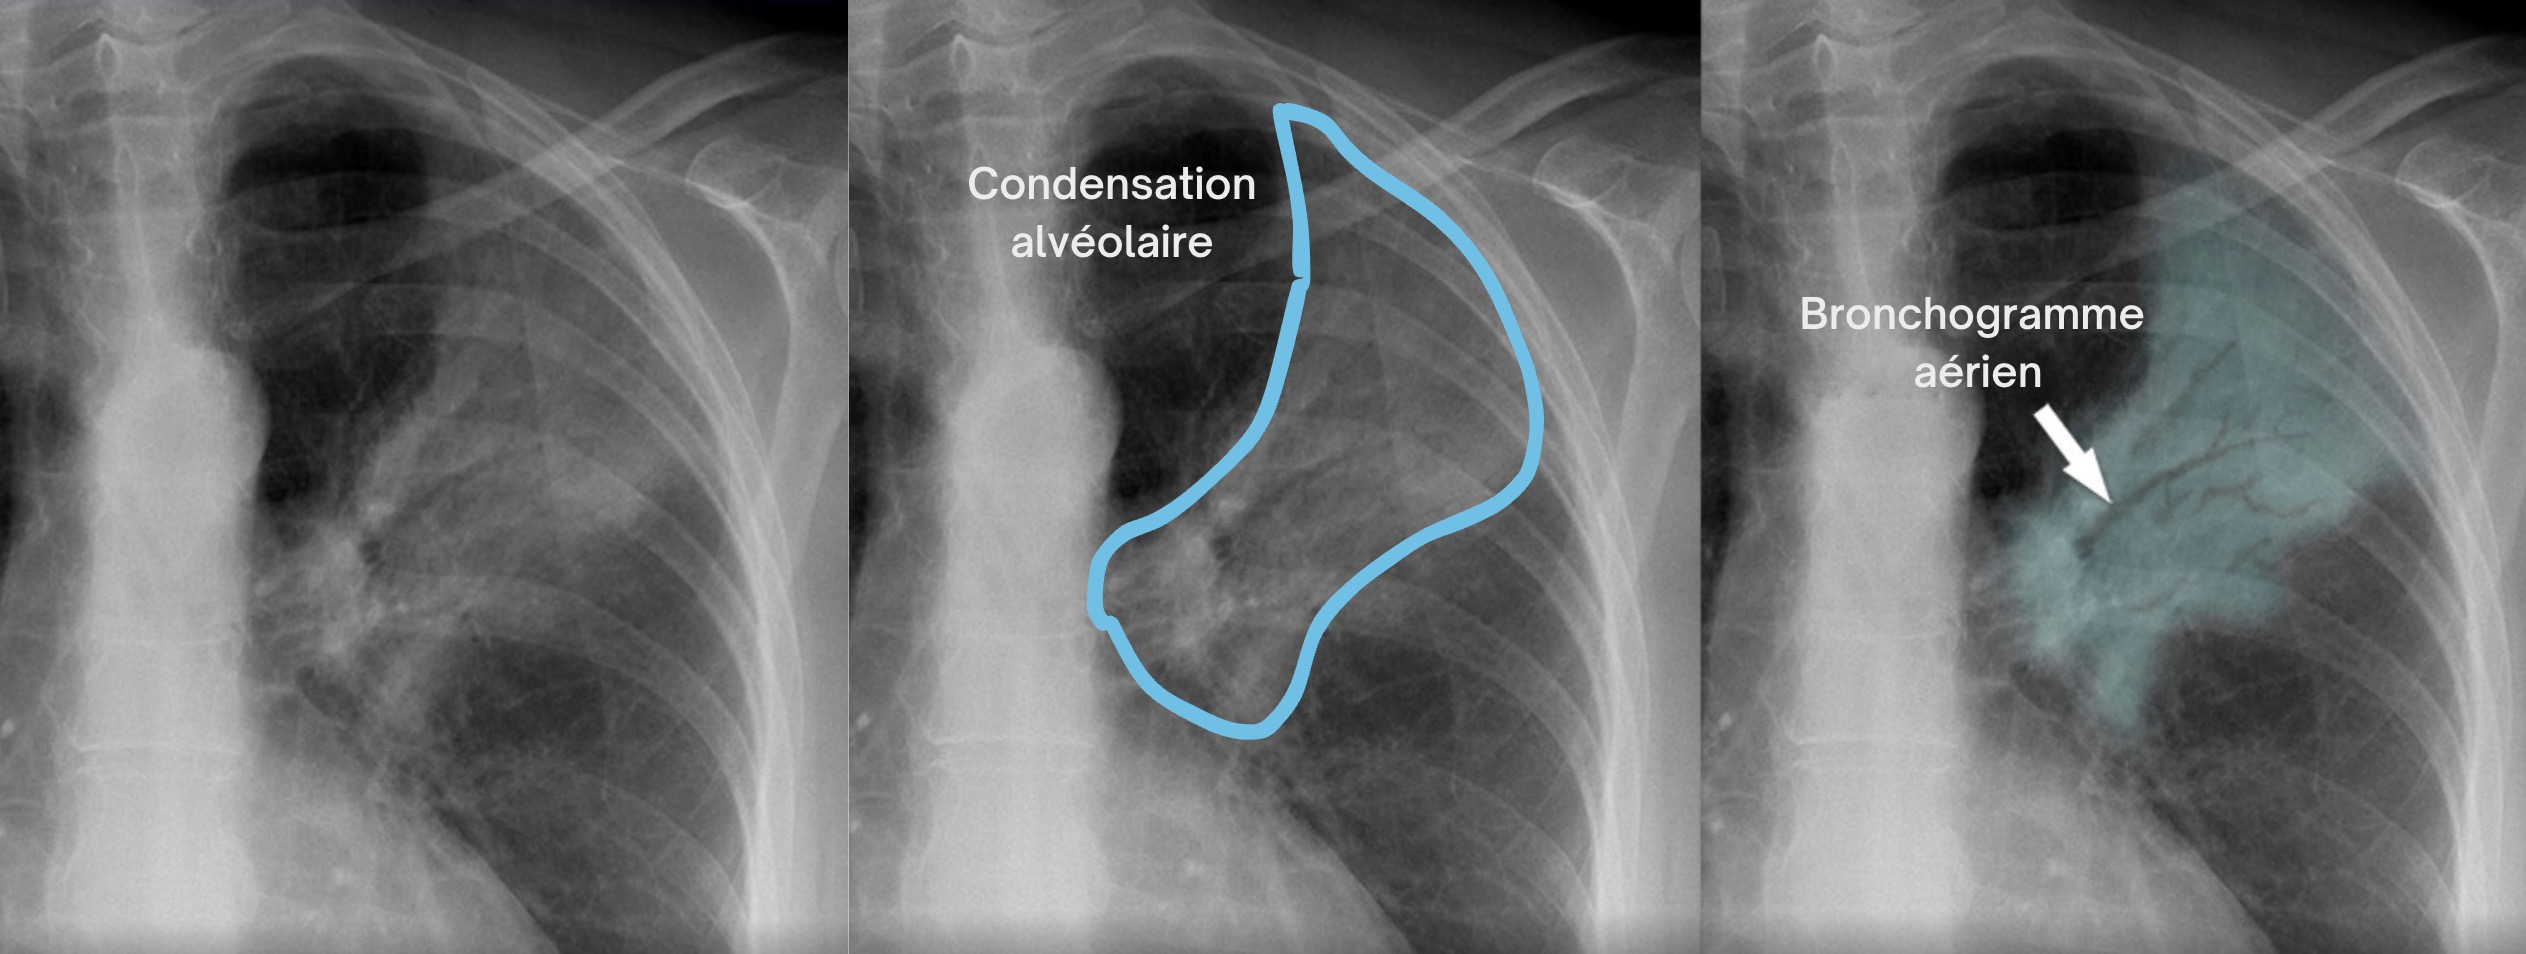

Ici, aucun de ces éléments n'est présent 👉 Le cliché montre au contraire une hyperclarté diffuse des deux champs pulmonaires avec des coupoles basses et des côtes horizontales, en parfait contraste avec l'aspect d'une pneumonie.

RP originale 👇

Réponse B: Vrai. La radiographie de Mr M. présente les 4 signes cardinaux de distension thoracique liés à l'emphysème :

Ces signes traduisent un emphysème, complication fréquente de la BPCO. Attention ! la radio seule ne confirme pas le diagnostic — elle oriente seulement.

Chez ce patient fumeur de 67 ans hospitalisé pour probable exacerbation (il y a un mois) le diagnostic de BPCO doit être au premier plan.